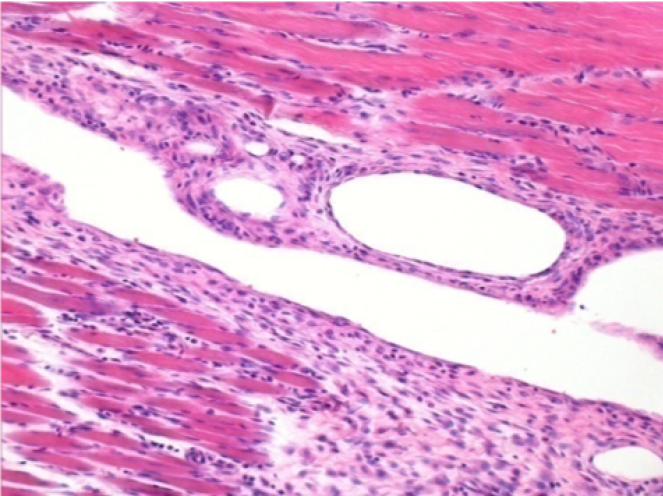

10 days after Endopeel Injection 0.1ml in the right pretibial muscle.

Here you may see the formation of the vacuoles which are surrounded by lymphocytes. Vacuoles are different from tissue necrosis . The presence of lymphocytes is related to the permeability of the cell membranes.